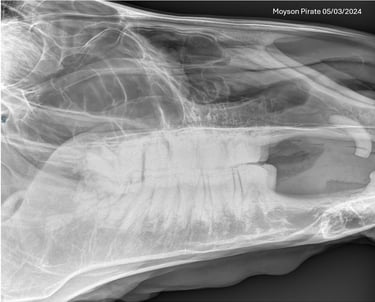

Is uw paard mank, hoefbevangen of is er een vermoeden van een halsprobleem? Dan kan het aangewezen zijn om een radiografisch onderzoek (RX) aan huis uit te voeren. Wij beschikken over een digitaal mobiel radiografietoestel, waardoor opnames eenvoudig bij u ter plaatse kunnen worden gemaakt.

Wij maken geen radiografische opnames in het kader van een radiografische keuring.

Dit onderzoek wordt uitgevoerd binnen een straal van 20 km rond de praktijk.